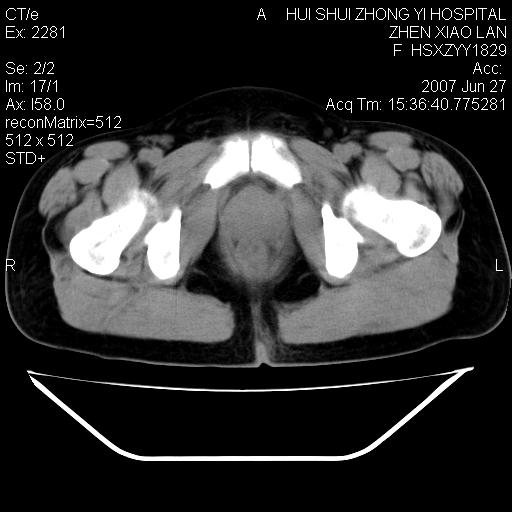

以下是引用还珠格格在2007-6-28 15:15:00的发言:[br]子宫明显增大,偏向盆腔右侧,密度均匀,和子宫同密度, 考虑 子宫肌瘤可能性大 建议增强 除外子宫平滑肌肉瘤。

以下是引用dyqct在2007-6-28 15:41:00的发言:[br]考虑多发子宫肌瘤可能性大,建议进一步增强检查。